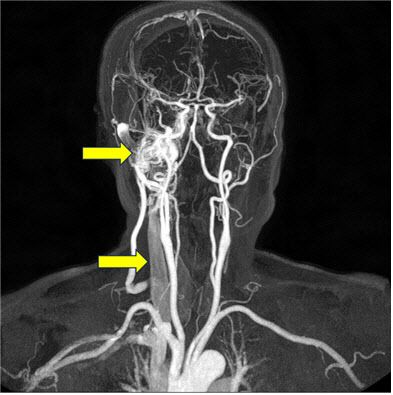

박동성 이명은 다양한 혈관성 질환이 원인일 수 있다. 그 중 하나는 동정맥루이다. 동정맥루는 동맥과 정맥이 비정상적으로 직접 연결된 상태로, 정맥으로 혈액이 비정상적으로 빠르게 이동하면서 전반적인 혈관 저항이 감소하고, 이것을 보상하기 위해 심장이 더 강하고 빠르게 뛰면서 귀에서 심장 박동 소리가 들리게 된다. 동정맥루를 방치할 경우 뇌신경병증, 뇌출혈, 뇌경색 등 다양한 합병증으로 이어질 수 있어 조기 진단과 치료가 중요하다.

경동맥 협착 역시 주요 혈관성 원인 중 하나이다. 경동맥의 좁아진 부위에서 혈액이 빠르게 흐르며 “두근두근”거리는 소리나 “와그락”거리는 소리를 일으키는 것이다. 협착이 심해질 경우 뇌졸중 위험이 급격히 증가하며, 보통 경동맥 협착을 지닌 환자는 심장병이나 말초혈관질환이 동반되는 경우가 많아 심근경색의 위험도 증가한다. 또한 빈혈, 갑상선기능항진증, 자궁근종 등 여성들이 흔히 호소하는 질환도 박동성 이명을 일으킬 수 있다. 심박수가 증가하고 혈류량이 늘어나면서 두근두근 소리가 들리는 것이다. 자궁근종과 박동성 이명은 직접적인 연관성보다는 자궁근종에서 발생하는 지속적인 출혈이 만성적인 빈혈을 유발하여, 혈류 및 혈압의 변화로 인해 박동성 이명이 발생하게 된다. 이는 적절한 치료를 통해 완치가 가능하다.

박동성 이명은 이비인후과적 문진 및 신체검사뿐만 아니라 다양한 혈관성 질환과도 연관이 되어있기에 혈관 조영 검사나 CT, MRI등의 영상 검사 진단이 필요할 가능성이 높다.